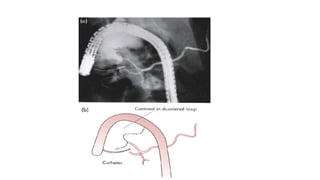

• Endoscopic retrograde cholangiopancreatography

Pancreatic Duct Anatomy •The duct of the ventral anlage becomes the duct of Wirsung, and the duct from the dorsal anlage becomes the duct of Santorini. • The ducts from each anlage usually fuse together in the pancreatic head • most of the pancreas drains through the duct of Wirsung, or main pancreatic duct, into the common channel formed from the bile duct and pancreatic duct.

• 14.

• The lengthof the common channel is variable. • In approximately 30% of patients, the duct of Santorini ends as a blind accessory duct and does not empty into the duodenum • main pancreatic duct is usually only 2 to 3 mm in diameter and runs midway between the superior and inferior borders of the pancreas, • Main pancreatic duct closer to the posterior than to the anterior surface

Investigation • Pancreatic functiontests • Estimation of pancreatic enzymes in body fluids • Imaging • Ultrasonography • Computed tomography • Magnetic resonance imaging • Endoscopic retrograde cholangiopancreatography • Endoscopic ultrasound